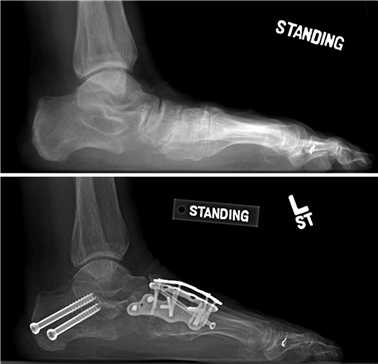

When conservative measures fail, the choice of procedure is dictated by the severity of the deformity, the presence of degenerative joint disease, and the stability of the first TMT joint. Distal osteotomies (e.g., Chevron) are generally reserved for mild to moderate deformities with an intermetatarsal angle (IMA) less than 13 degrees. Diaphyseal osteotomies (e.g., Scarf) offer greater translational correction for moderate to severe deformities. Proximal procedures, such as the Lapidus arthrodesis, are indicated for severe deformities (IMA > 15 degrees), clinical hypermobility of the first TMT joint, or recurrent hallux valgus. For hallux rigidus, joint-sparing procedures like cheilectomy are indicated for early-stage disease, while first MTP arthrodesis remains the gold standard for end-stage arthritis.

Weight-bearing anteroposterior (AP), lateral, and sesamoid axial radiographs are mandatory. On the AP view, the surgeon measures the Hallux Valgus Angle (HVA, normal < 15°), the Intermetatarsal Angle (IMA, normal < 9°), and the Distal Metatarsal Articular Angle (DMAA). The lateral view is scrutinized for Meary's angle (talo-first metatarsal angle) to identify midfoot collapse, as well as the presence of dorsal osteophytes indicative of hallux rigidus. The sesamoid axial view is critical for assessing the degree of sesamoid subluxation and the integrity of the crista.

Positioning of the fusion is the most critical step of the operation. The hallux must be positioned in 10-15 degrees of valgus, 15-20 degrees of dorsiflexion relative to the first metatarsal, and neutral rotation. Excessive dorsiflexion causes shoe impingement, while insufficient dorsiflexion leads to vaulting during gait and interphalangeal joint arthritis. Fixation is most reliably achieved using a pre-contoured dorsal locking plate combined with a lag screw crossing the fusion interface.